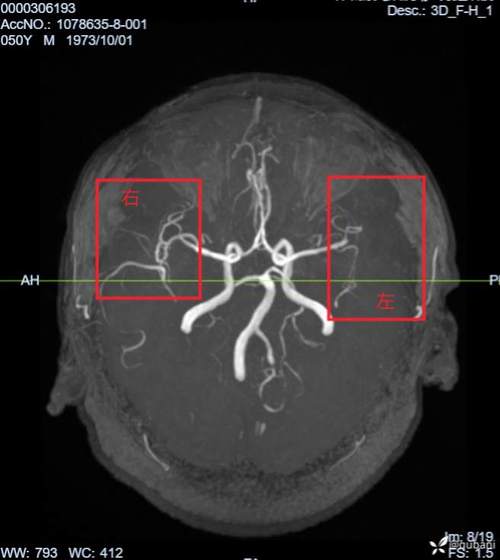

磁共振血管成像(MRA)

- 作用:无需注射造影剂(或使用少量造影剂)即可清晰地显示颅内大血管(如颈内动脉、大脑中动脉等)的情况,医生可以通过MRA判断导致脑梗死的“罪犯血管”是否存在狭窄、闭塞、夹层或动脉瘤等病变,这对于明确病因、制定后续治疗方案(如支架植入)至关重要。